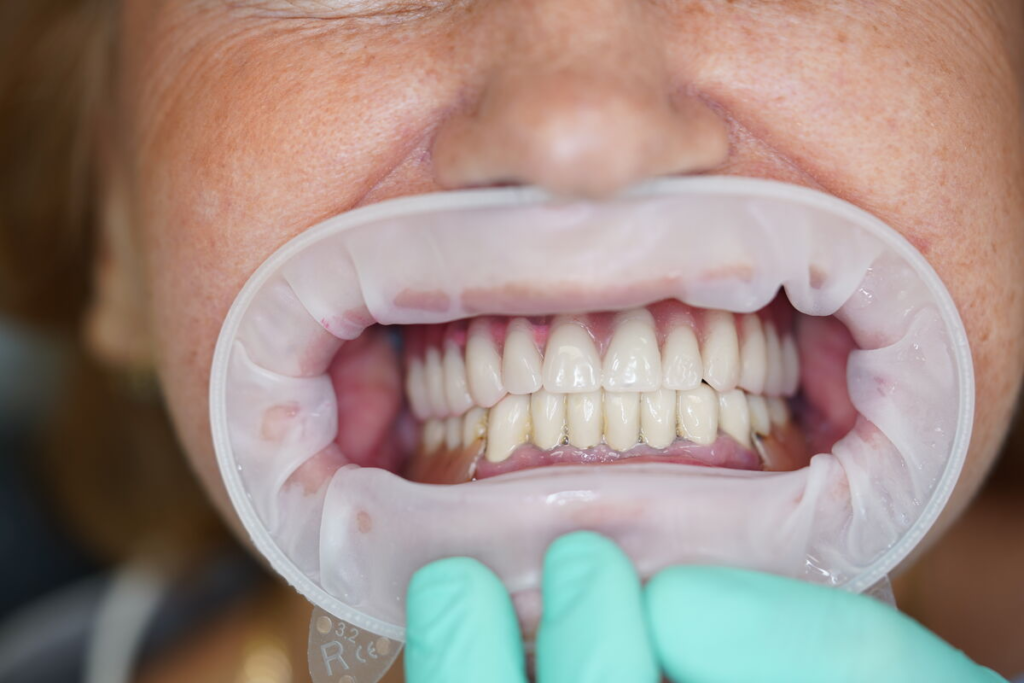

Odcházíte s pevnými dočasnými zuby — bez snímatelné protézy.

Můžete mluvit, smát se a jíst měkkou stravu.

Používáme multivrstvý zirkon pro maximální estetiku, pevnost a dlouhou životnost.

Výsledky, které mluví za vše

Ukázky práce před a po